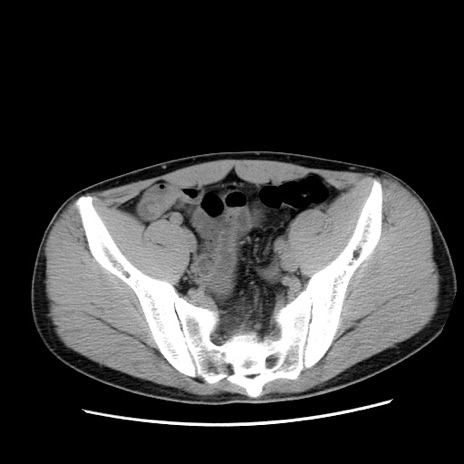

冠状断像

症例36(横断像)

【症例】20歳代 男性

【主訴】心窩部痛

【現病歴】今朝より上腹部痛あり。一旦軽快していたが再度出現したため救急要請。昨日夕に白身の魚を含む刺身を食べた。

【身体所見】BP 136/89mmHg、HR 74/min、BT 37.0℃、腹部:膨満、軟、心窩部に圧痛あり。反跳痛なし、筋性防御なし、腸雑音やや亢進あり。

【データ】WBC 17700、CRP 0.48